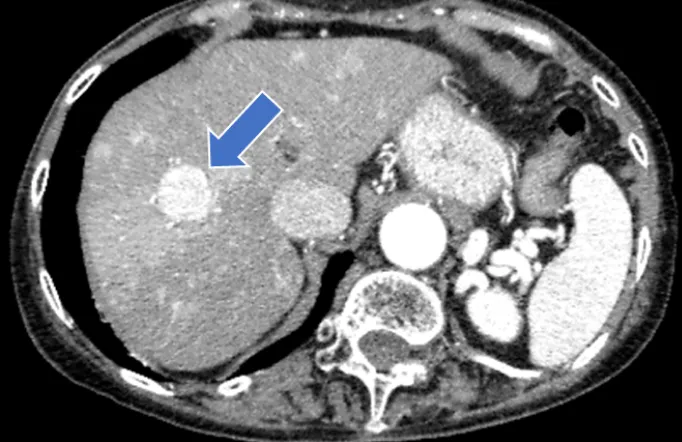

肝がんの検査には、血液検査と超音波(エコー)検査(写真2)、CT検査(写真3)、MRI検査といった画像検査を組み合わせて行います。CT検査やMRI検査では造影剤を使用して詳細な検査を行いますが、腎機能低下や透析症例でも安全に使用できる「造影剤」を用いて行う造影エコー検査(写真4)も週1回外来で行っています。

• (写真3)肝がんの造影CT写真